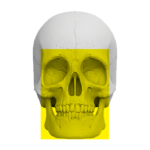

Zakres pracy tomografu.

(Badanie CBCT)

Twarzoczaszka

( 16 cm x 17 cm )